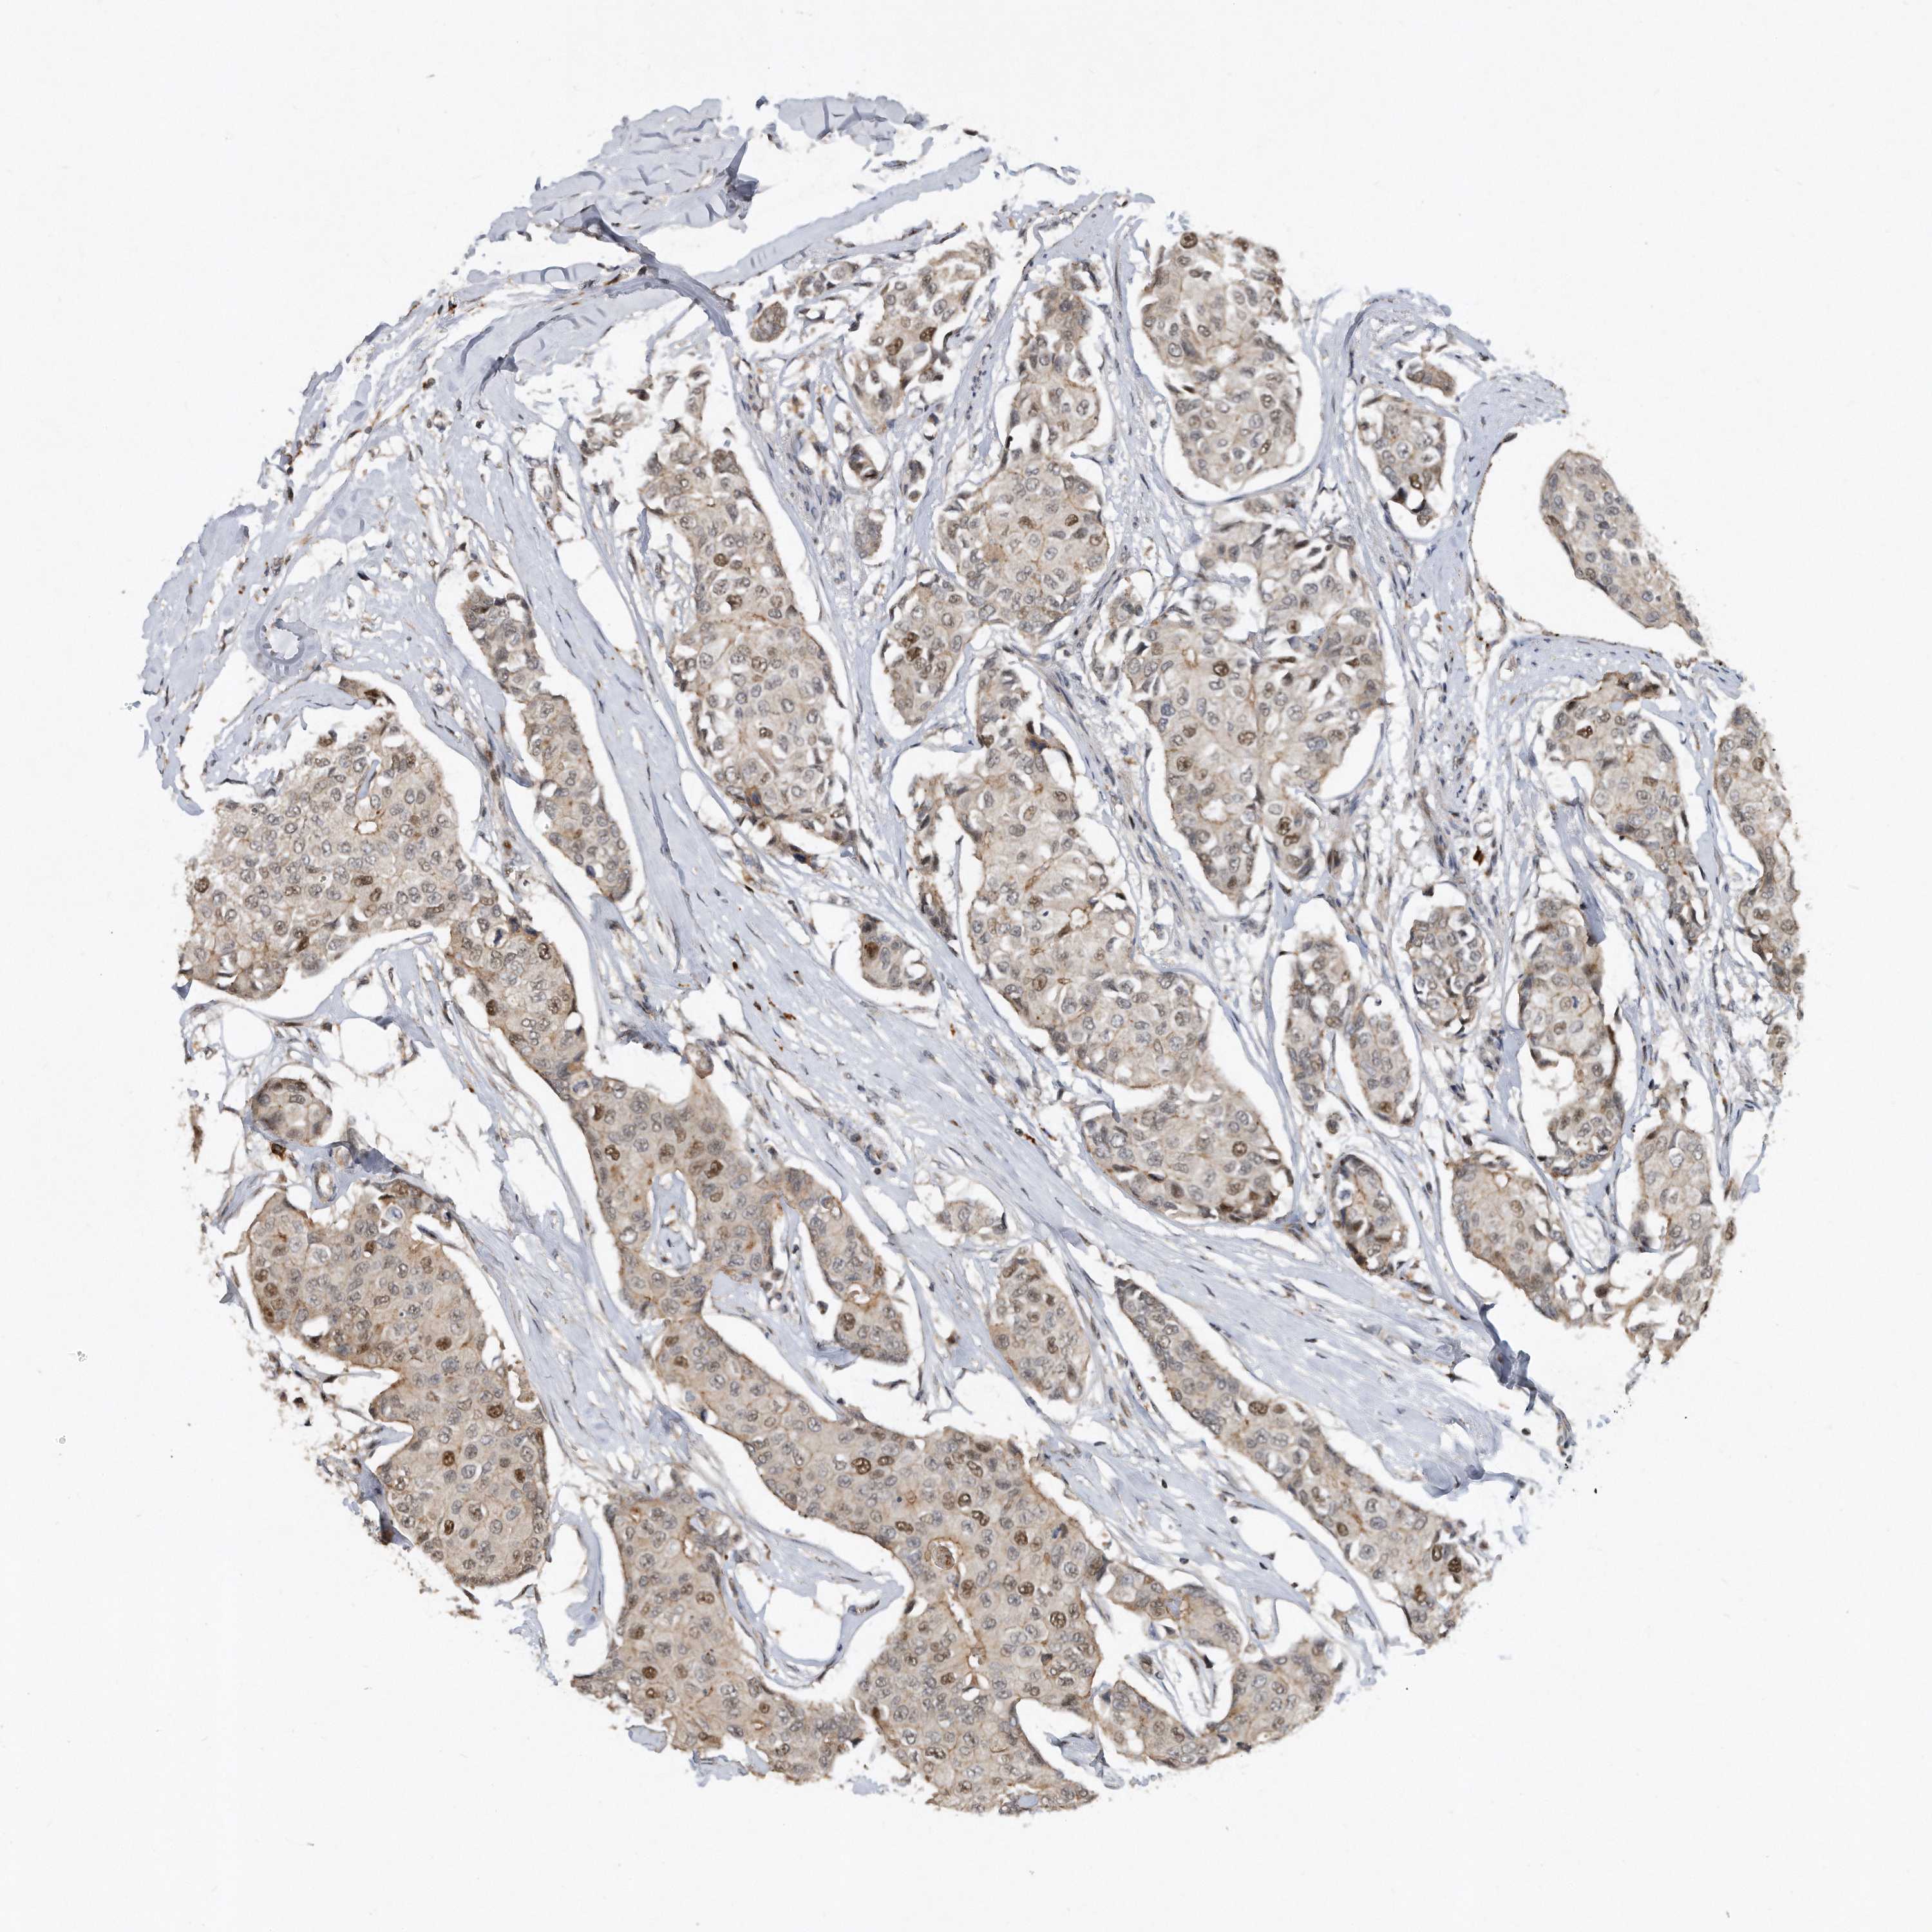

BRCA TCGA BRCA VALIDATION PROTEIN EXPRESSION

ANTIBODIES

AND

VALIDATION